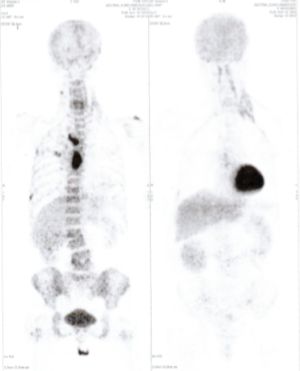

Below are some of the cases, from more than 80 cases we have treated so far with good results. When reading the PET/CT scans, the picture on the left is before treatment, and the picture on the right is after treatment. The intensity of black represents the activity of the cancer, but some black areas are not cancer: brain, heart, radioactive urine in bladder. For the heart, the intensity of black depends on the number of hours of fasting: if more than 10 hours, the heart is not even black, but if fasting is less than 6 hours, it is very black. The intensity of black in the brain can be variable in different scans depending on the brain activity at the time of the scan. The intensity of black in the radioactive urine can also be variable due to the hydration of patients and the time of injection of diuretic.

CASE NO: 1

(HEPATOCELLULAR CARCINOMA + STOMACH CANCER)

A middle-aged women who is very thin and very weak, can hardly walk, lying in bed most of the time. She saw a cancer specialist in a top hospital who discovered that she had massive hepatocellular carcinoma, and another cancer in the stomach. Given that hepatocellular carcinoma is incurable and stomach cancer is very difficult if not impossible to cure without surgery, she was told that nothing could be done for her. She came to ask us to help her. After just 4 treatment, the hepatocellular carcinoma went into remission, and the stomach cancer (arrow) became less active. Until today, more than 6 months later, the hepatocellular carcinoma is still in remission.

CASE NO: 1 - A FEW MONTHS LATER

A few months after successful treatment for hepatocellular carcinoma, and partially successful for stomach cancer, the PET/CT scan showed the stomach cancer becoming very active, with several metastases to the parts of the liver not previously involved by hepatocellular carcinoma. After a few treatment, all the active stomach cancer lesions in the stomach and in the liver went into remission.